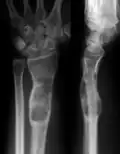

| X-ray image showing enchondromas localized in the lower part of the radius of a 7-year-old girl with Ollier disease. | |

Abnormal bone growth such as shortening or thickening and deformity may be observed in patients of Ollier disease. These bone lesions are visible at birth using radiography but are usually not screened or examined for until clinical manifestations present during early childhood. However, some patients may exhibit no signs of any symptoms.[1] One study found thirteen to be the mean age of diagnosis in patients with Ollier disease. In an X-ray, there would normally be the presence of several homogeneous lesions of an oval or elongated shape with bone edges that are slightly thickened.[3] With age, these lesions may calcify and appear as diffusely minute spots or stippled. Fan-like septations or streaks would be indicative of the presence of several enchondromas. Early detection and consistent and repeated monitoring is important in order to prevent and treat any potential bone neoplasms.